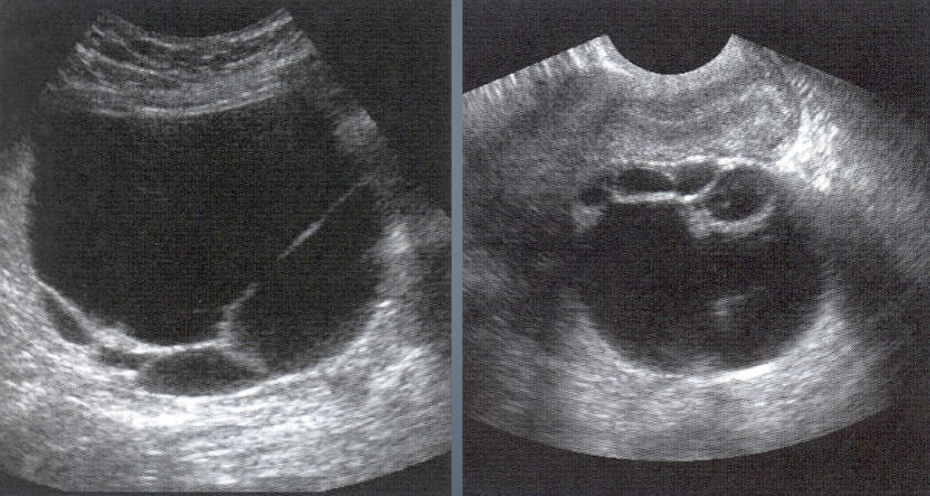

Theca Lutein Cyst

largest of functional cysts

may range in size from 3-20 cm

multiloculated, bilateral fluid filled

patients will have high hCG levels

often associated with Gestational Trophoblastic Disease (Molar Pregnancy)

Theca Lutein Cysts tend to appear:

Multi-loculated

thin-walled

large

bilateral